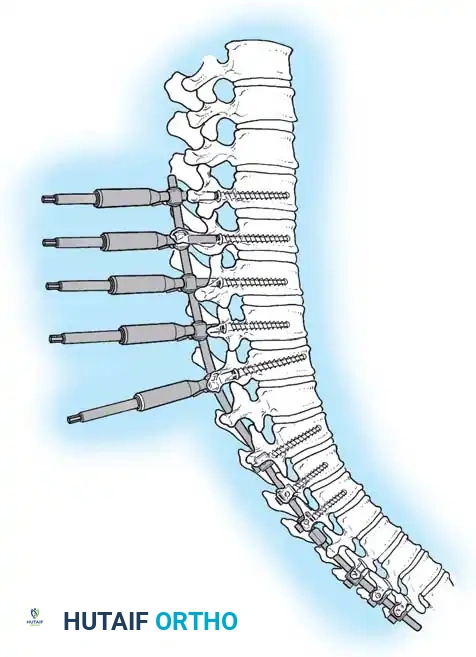

Diagram illustrating the placement of pedicle screws and the site of posterior column osteotomies.

3. Pedicle Screw Instrumentation

Free-hand or navigation-assisted pedicle screws are placed bilaterally. High implant density is crucial at the apex (to allow for powerful reduction forces) and at the cranial and caudal foundations (to prevent pullout).